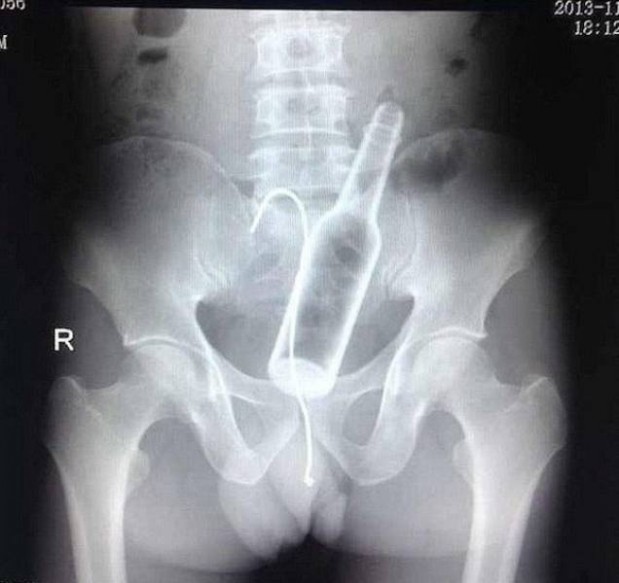

#10 Miehen jumissa oleva seksilelu ja pihdit, joilla hän yritti saada sen pois